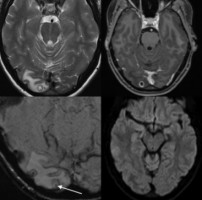

머리 아파 병원 갔더니 뇌 속에 기생충이 가득

머리 아파 병원 갔더니 뇌 속에 기생충이 가득체내에 기생충 자라는 '신경낭미충증'덜익은 돼지고기 먹으면 나타날 수 있어근육·피부·안구에서도 기생충 서식 가능호주 본토서 처음 발생한 희귀 질환수년간 두통을 호소해 온 한 호주 여성의 뇌에서 커다란 기생충들이 자라는 희귀질환이 발견돼 충격을 주고 있다.4일(현지시간)CNN방송…